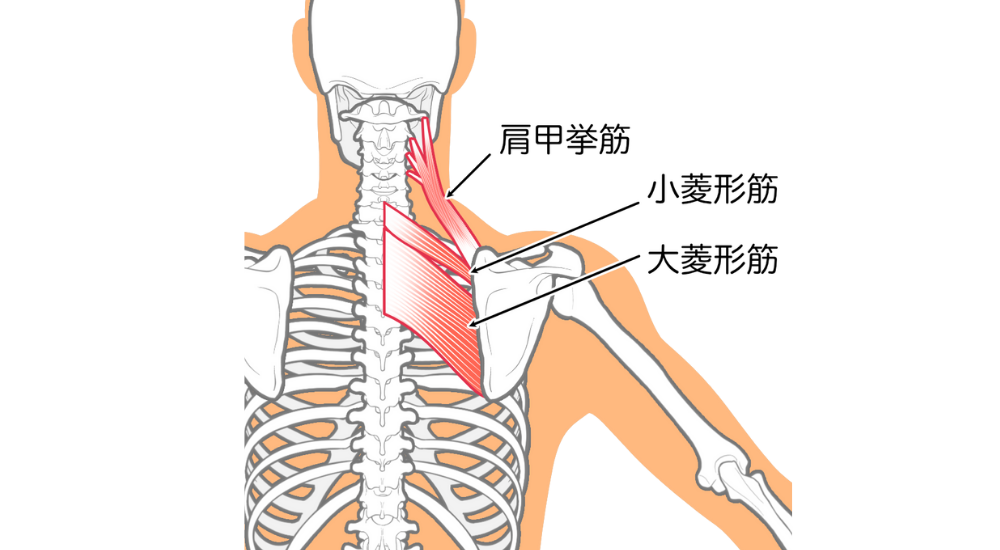

- 僧帽筋(上部)・肩甲挙筋: 首から肩にかけての筋肉。ストレートネックや猫背で頭部を支えるために過剰に緊張し、肩凝りや首の痛みの原因となります。

- 菱形筋: 肩甲骨と背骨の間。猫背で引き伸ばされて硬くなり、肩甲骨内側の凝りや痛みの原因となります。